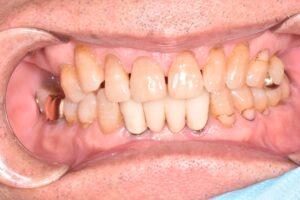

右上の前歯を転倒により強打し、歯根が破折してしましました。

抜歯直後の口の中の写真です。

抜歯と同日に仮の歯を入れることで見た目の改善を図っています。この時は噛み合わせを全く与えていないため、隣の歯よりも短くしています。

また、抜歯を行うと残っていた周囲の骨が吸収し審美的に不利になるため、抜歯と同時に歯槽堤温存術(Alveolar ridge preservation)と呼ばる方法で、可能な限り骨が吸収しないような治療を併用しています。

この状態で歯ぐきや歯槽骨が治癒するのを待ってから最終的な歯を作製していきます。